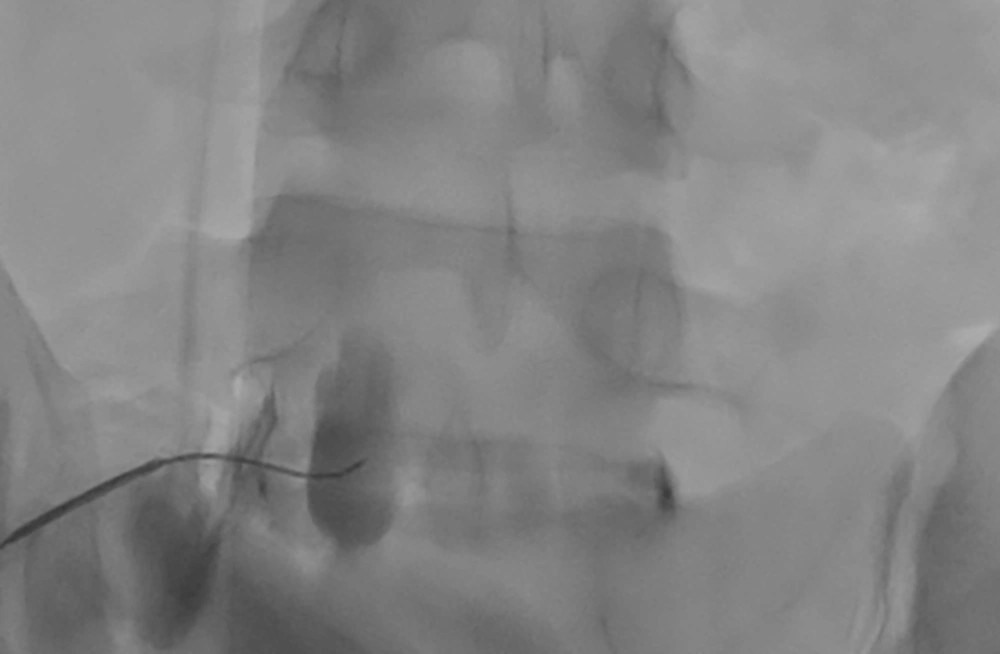

Fluoroscopic imaging was utilized to visualize the L-S spine. Anteroposterior (AP) views were obtained. Subsequently, an oblique C-arm tilt was used to achieve a ‘scotty dog view’ by overlapping the L5 spinous process with the contralateral facet line. Finally, a cephalad C-arm tilt was performed to displace the iliac crest from the field of view. After local anesthetic infiltration of the skin and subcutaneous tissue, a 20-gauge, 150 mm spinal needle with a curved tip was advanced. The needle entry point was established lateral to the lower L5 vertebral body, just cephalad to the iliac crest. A coaxial approach was employed to contact the lower L5 vertebral body. Lateral fluoroscopic imaging confirmed needle depth, and the needle was then wiggled anteriorly until positioned slightly anterior to the L5-S1 disc. The AP fluoroscopy view verified the needle tip location at the junction of the lateral and mid-third of the vertebral body. Contrast injection with Omnipaque 300 demonstrated unilateral (right-sided) spread anterior to the L5-S1 disc (Figure 2). A total of 10 mL of 0.25% bupivacaine mixed with 4 mg of dexamethasone was administered.

For complete coverage of the superior hypogastric plexus, a left-sided procedure was attempted. Due to anatomical variation, specifically an enlarged left transverse process, the intended posterolateral approach was not technically feasible. Consequently, a trans-discal approach was utilized. Fluoroscopic guidance aimed to provide an unobstructed view of the anterolateral L5-S1 disc. This was accomplished by obtaining AP views and squaring off the lower L5 and upper S1 endplates. An oblique C-arm tilt, approximately 20°, was used to clear the S1 superior articulating process (SAP) and lamina from the needle path.

The entry point was positioned just lateral to the S1 SAP. Excessive obliquity was avoided to prevent the iliac crest from obscuring the view and to prevent nucleus pulposus penetration. A double-needle technique, employing an 18G introducer with a 22G needle, was considered to reduce the risk of discitis. A coaxial view was utilized to guide the needle to the posterolateral aspect of the L5-S1 disc. AP and lateral fluoroscopy views confirmed the appropriate needle trajectory. Then, the needle was advanced through the lateral third of the disc, extending just anterior to its border. Loss of resistance confirmed needle passage beyond the disc. Contrast injection demonstrated anterior spread (Figure 3). A total of 10 mL of 0.25% bupivacaine mixed with 4 mg dexamethasone was injected uneventfully.